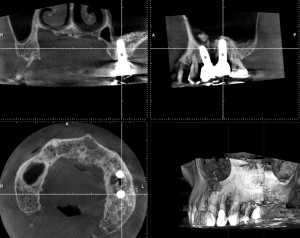

根管治療で現在通院中のNさん。6年前にサイナスリフトを行い2本インプラントを埋入したが順調に経過しているようだ。この時は上顎洞の窓開けを行いたい場所に隔壁があり、これを避けるために2つ小さめの窓を開けて行った。非常にやりずらく苦労した覚えがある。今回は反対側の歯に根尖病変が見つかったので根管治療となった。以前より折れ込んでいたと思われる金属の器具の破片を除去して始めているが、うまく治ってくれるだろうか。S先生のコースに行っている成果を出したいものだが、歯科治療の中でも水ものと言われる再根管治療は、一筋縄ではいかないこともある。とりあえず、インプラントの経過が良くてほっとした。

サイナスリフト6年経過例